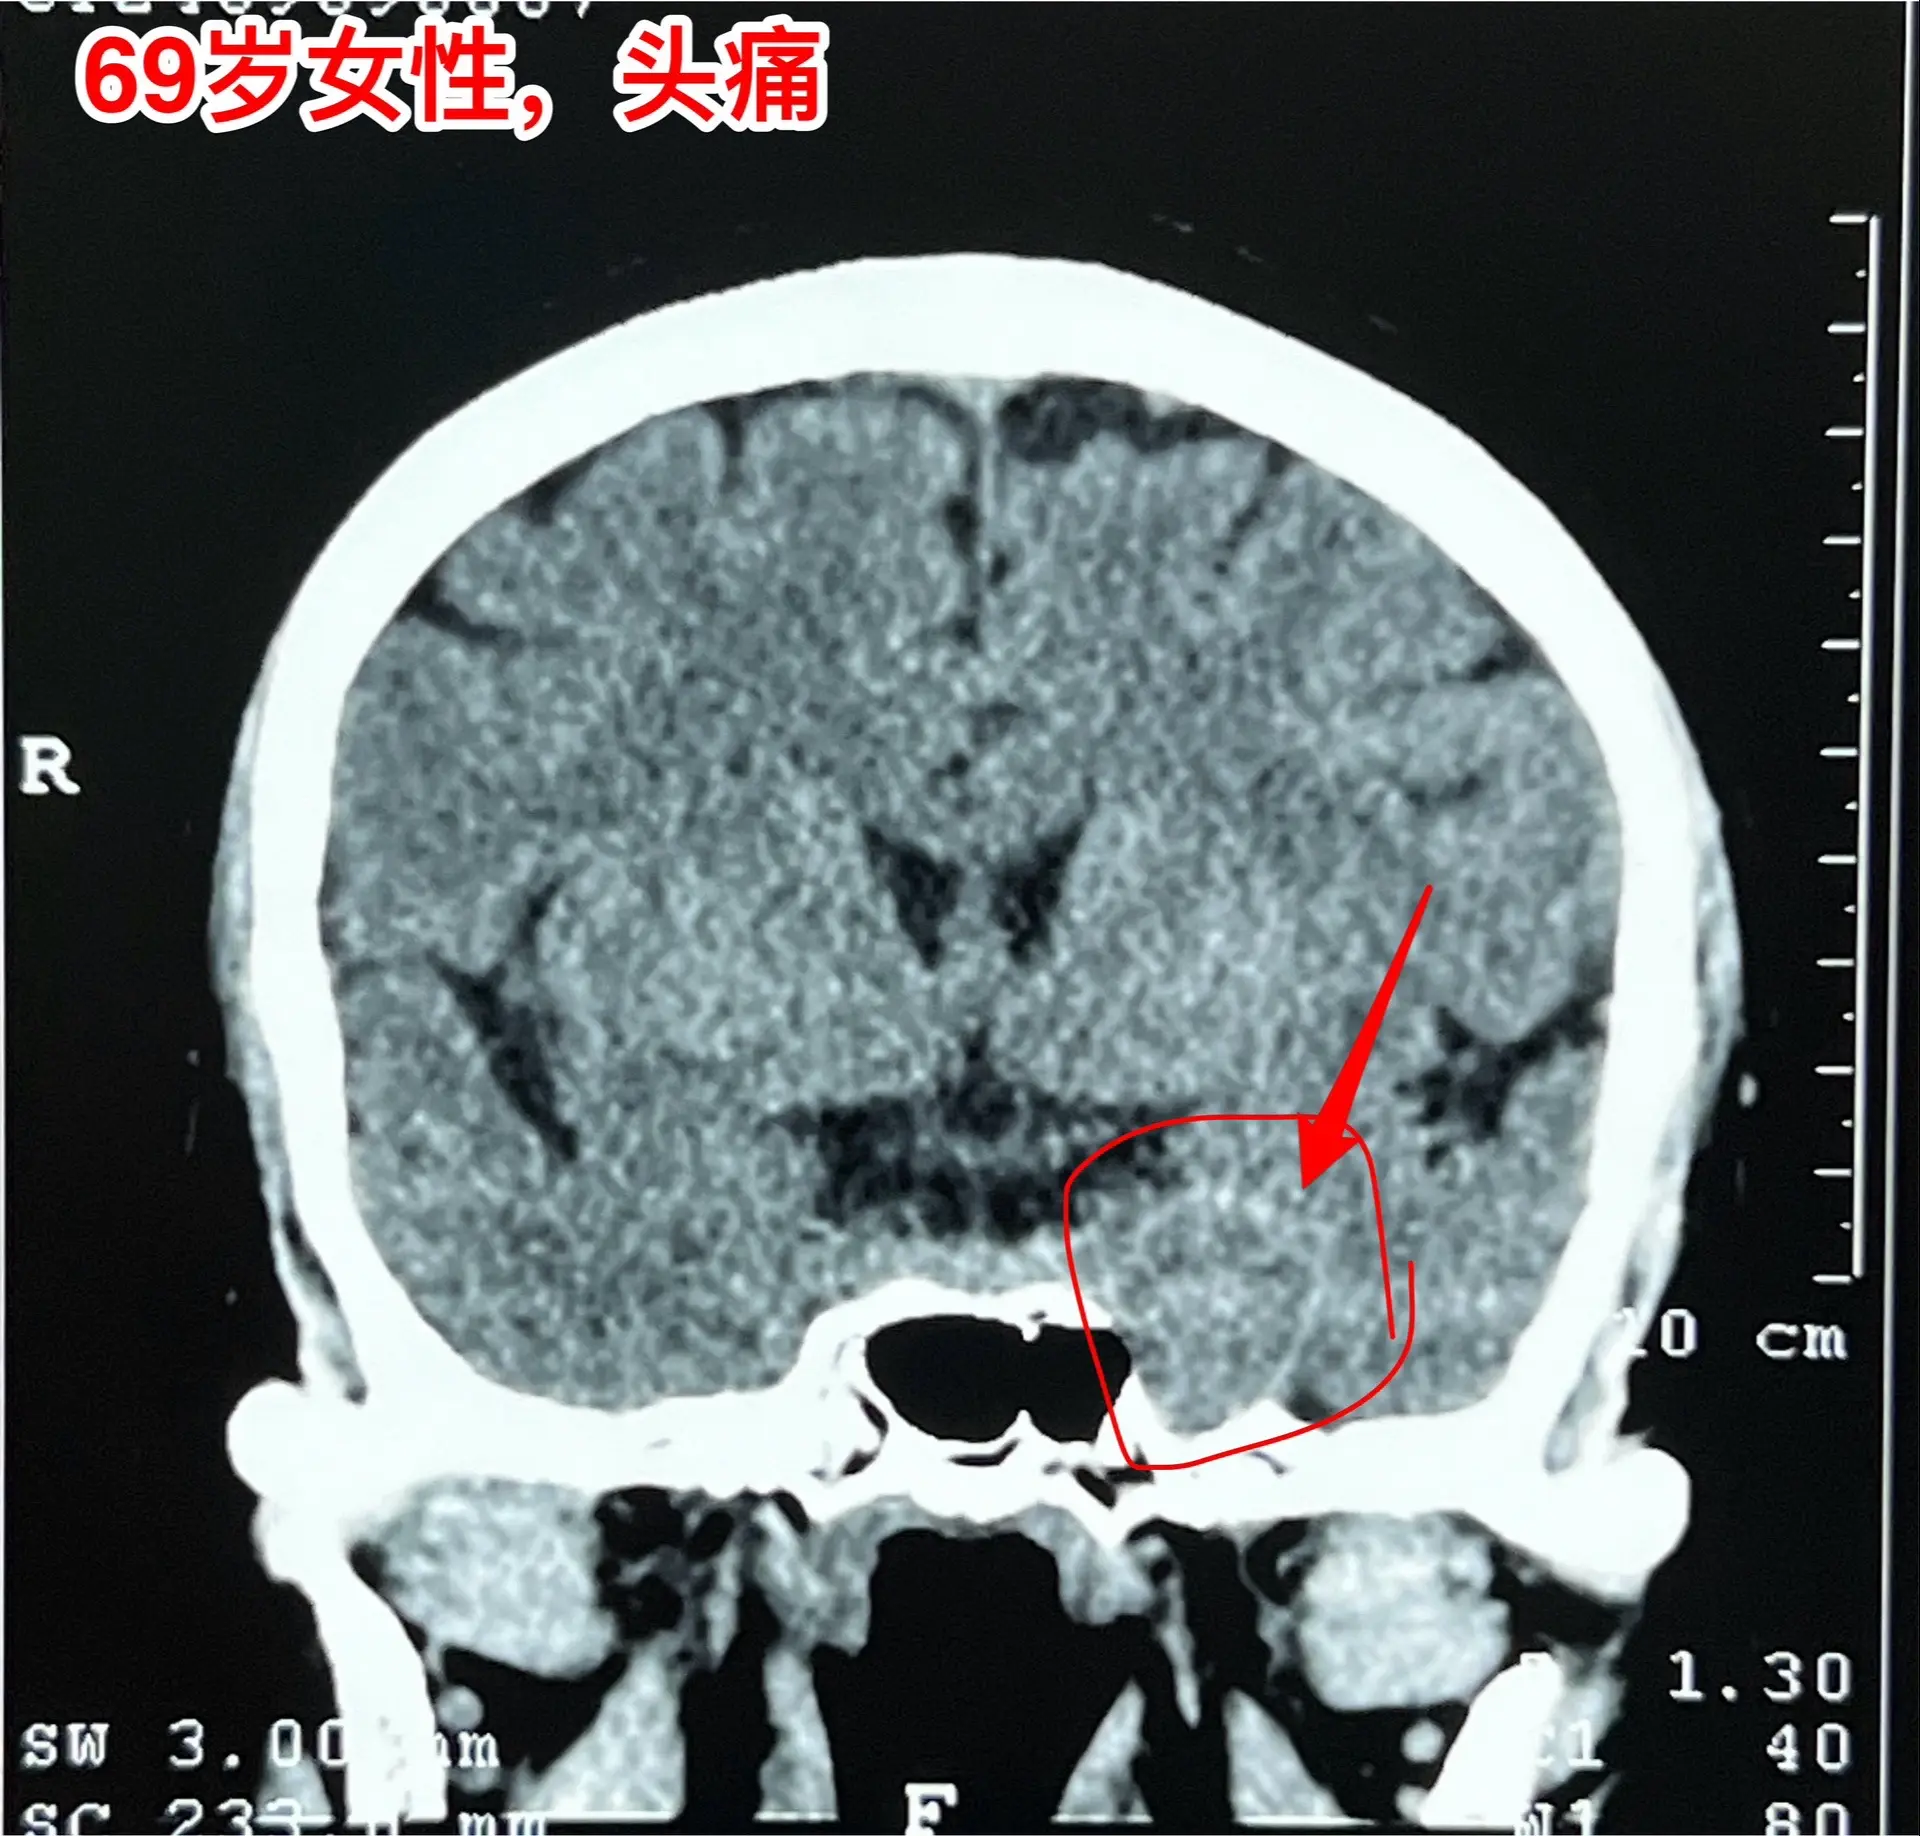

海绵窦区神经鞘瘤,是良性肿瘤。69岁青岛市老太太经常感到头痛,不太剧烈,没有专门去检查。九月份检查脑部磁共振发现左侧海绵窦长了肿瘤。在我院住院后作了强化磁共振,看见左侧海绵窦内有个大肿瘤,见图,考虑是神经鞘瘤,神经鞘瘤是良性肿瘤,如果完全切除了就可以治愈。 老太太有两个女儿,积极要求给她作手术。69岁年龄还是有点大,手术是有风险的! 9月12日下午四点开始进入手术室,手术持续到13日凌晨才结束。手术过程很顺利,肿瘤得到完全切除。今天看见老太太精神比较好,准备下地行走。神经鞘瘤海绵窦